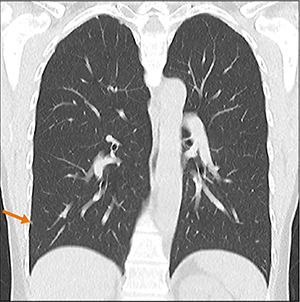

図1 胸部検診撮影

CTDIvol=0.128 mGy、DLP=4.8mGy・cm、実効線量=0.06mSv

AiCE-i再構成で最大3mmの結節のほか複数の微小結節まで、通常CTで確認できたすべての結節を検出できた。肺野はもとより、肺尖部、肺底部もよく観察できる。縦隔も許容範囲と読影医から評価。